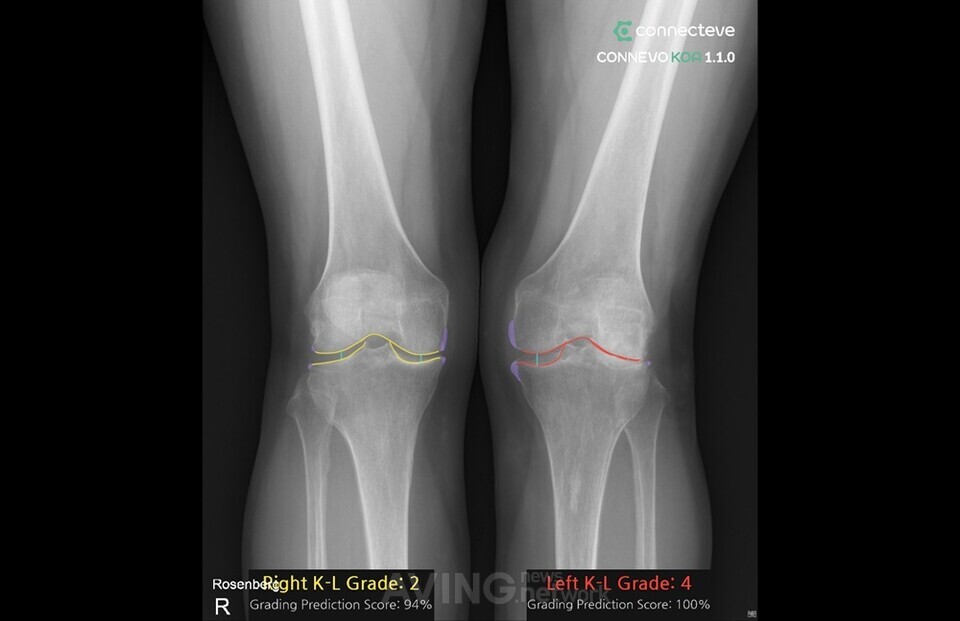

CONNECTEVE X

인공지능 기반 X-ray 이미지 근골격 정밀 분석 시스템

현재 ![]() 코넥티브 한국∙스타트업 | ![]() CONNECTEVE X 인공지능 기반 X-ray 이미지 근골격 정밀 분석 시스템 | 인공지능 | 바이오/의료 이미지/영상 | Series A 알 수 없음 |